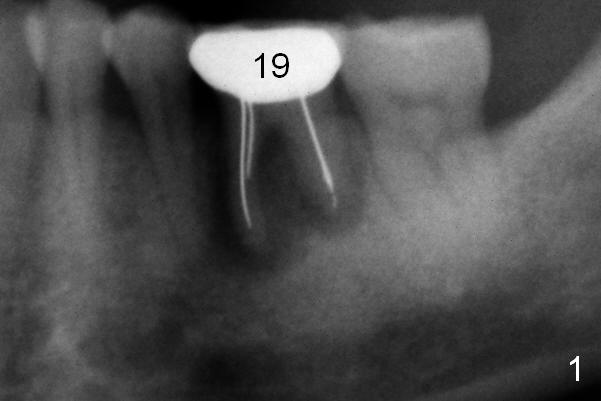

A 50-year-old man (CZ) requests implant restoration at the tooth #19 (Fig.1). After Metronidazole, a large (5 mm and up) immediate implant is going to be placed deep (Fig.2 green) with an abutment (blue) with long cuff (3 or 4 mm, pink). A large amount of bone graft (red) placed around the implant and against the distal root surface of #20. Osteotomy is initiated in the septum. If the height of the latter is more than 7 mm (take preop PA), set stopper at 7 mm (shortest). Otherwise open Magic Sinus Kit or Sinus Master Kit (shortest stopper 1 and 2 mm, respectively). Also take preop photos to show whether there is buccal or lingual gingival recession. Two dummy implants (5x9, 5x11 mm) will try in. If they are placed too deep, more than 4 mm from the gingival margin, switch to UF or SM. The cemented abutment's cuffs are longer, 5 or 6 mm.